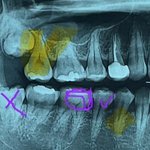

교정 함부로하면 안돼 진짜..

나같은 케이스는 교정 비발치가 나음

발치

가 나음?

[꼭봐주세요] 비

교정으로 뻐드렁니가 되었는데.. 치아를 이런...